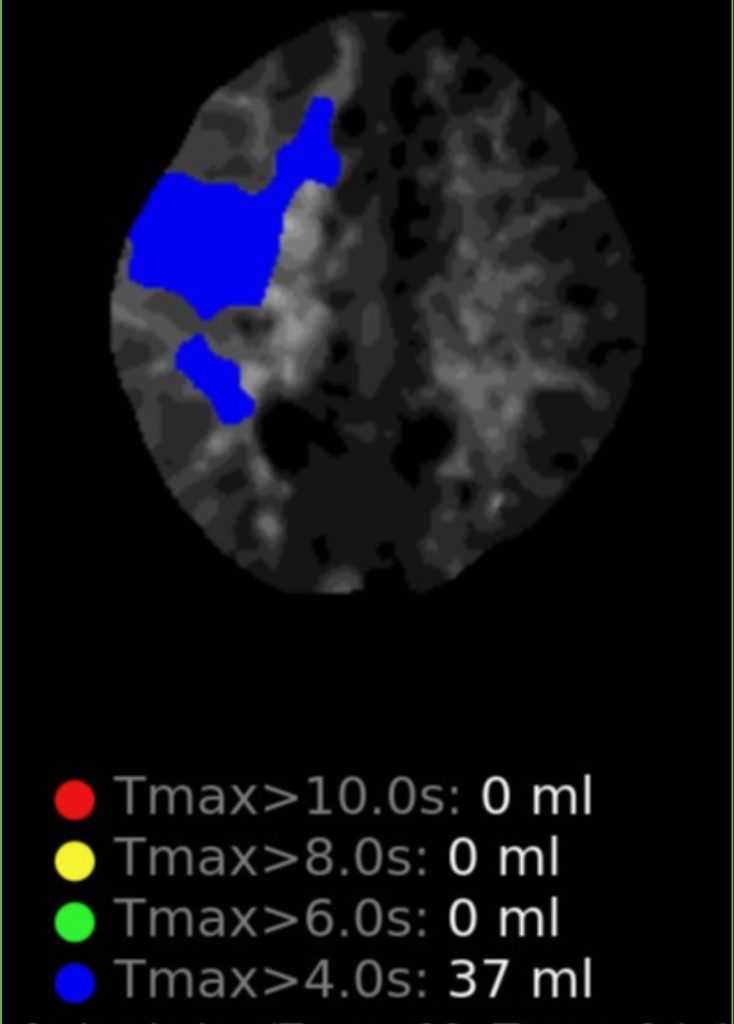

Figure 2

Noninvasive vascular imaging was sufficiently suggestive to warrant conventional digital subtraction angiography, performed by Dr. Brisman and confirming Moya-Moya syndrome (Figures 1). CT Perfusion (Figure 2) showed a decreased transit time of blood to the right hemisphere and the patient was recommended to undergo cerebral revascularization to avert stroke.